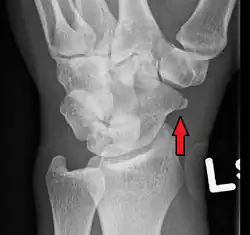

Radiolucency around a 12 days old scaphoid fracture that was initially barely visible.[11]